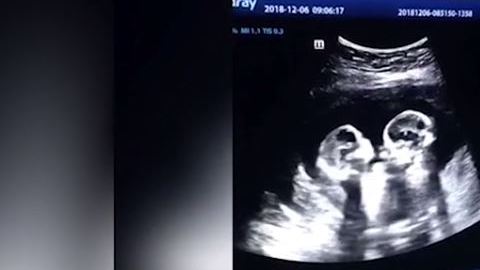

Las gemelas parecieran darse unos cuantos golpes. Crédito: Foto tomada de video

En el ultrasonido se puede ver el momento exacto en el que estas gemelas pareciera que estuvieran peleando entre ellas, pues hacen movimientos como si se patearan o golpearan mutuamente con sus manos.